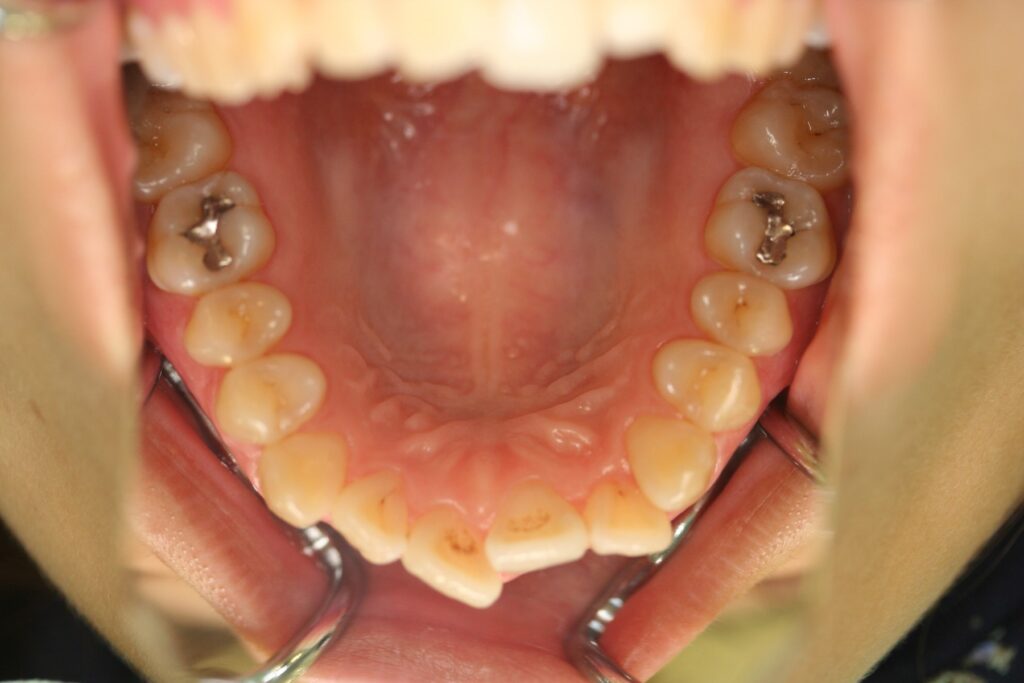

治療実績(症例) アライナー矯正 症例1 上顎前突症例 症例2 上下顎前突症例 症例3 叢生 症例4 開咬 症例5 開咬(外科的矯正治療) アライナー矯正 Post Share Hatena Line RSS feedly Pin it note 1.主訴2.診断名3.初診時年齢4.治療に用いた主な装置とオプション5.抜歯部位6.治療期間・通院回数7.総額と費用内訳総額相談検査・診断料調整料4,000円8.リスク・副作用 治療前 治療中 治療後